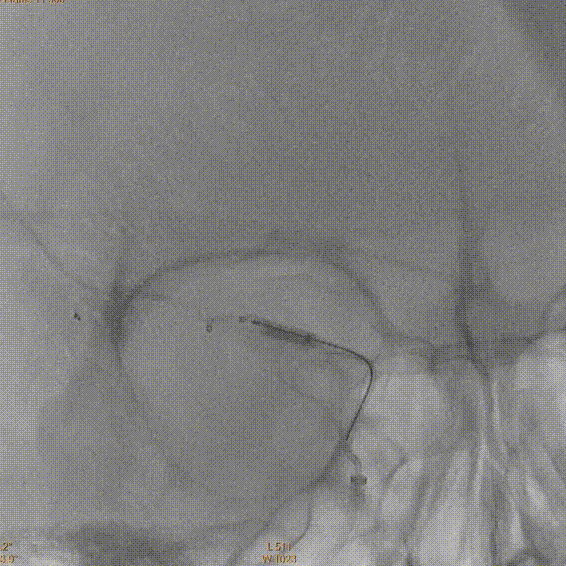

术前MRA:右侧大脑中动脉闭塞。

评估病变及代偿:Ⅰ型弓,右侧大脑中动脉闭塞,软脑膜动脉、大脑前动脉对其部分代偿,ASITN/SIR 2级。

术前DSA造影